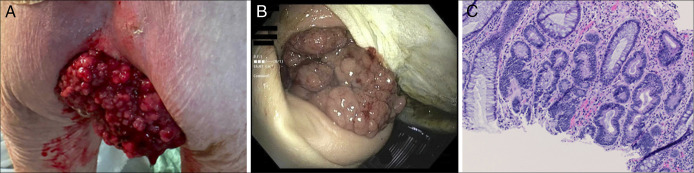

Large Tubulovillous Rectal Mass Causing McKittrick-Wheelock Syndrome.

引起McKittrick-Wheelock综合征的大管绒毛状直肠肿块。